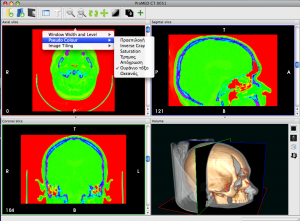

InVesalius is an image processing software dedicated to DICOM images (“.dcm” / “.DCM” extension) produced by imaging equipment (CT, MRI). It is fully compliant with the DICOM standard for image communication and image file formats. InVesalius is able to read 2D images and build 3D models of the region of interest.

InVesalius has been designed for navigation and visualization of multidimensional images: 2D viewer and 3D viewer and also for rapid prototyping anatomical structures. The 3D Viewer offers all modern rendering modes: Multipla

nar reconstruction (MPR), Surface Rendering, Volume Rendering and Maximum Intensity Projection (MIP). Surfaces created by InVesalius can be exported to OBJ, STL or other 3D files supported by Blender or other software. It is completely written in Python. Also, we only use free software tools in its development, including VTK (Visualization Toolkit), wxPython, GDCM (Grassroots DICOM), ITK (Insight Toolkit), NumPy, PIL (Python Imaging Library).